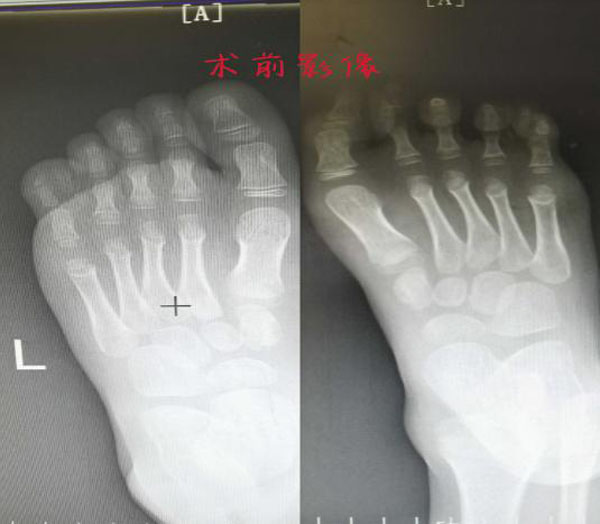

经过初步查体,见小哲双足六趾多趾畸形,甲相连,共趾蹼,5.6趾并趾畸形,以“双足第5趾并趾畸形”诊断住院。术前,手·显微外科团队为小哲精心设计了手术方案,5月3日,小哲成功接受了“双足第五趾多趾切除并趾分离术”,手术顺利。术后第二天,小哲已经能和小朋友在病房里开心的玩闹了,小哲的父母也露出了开心的笑容。